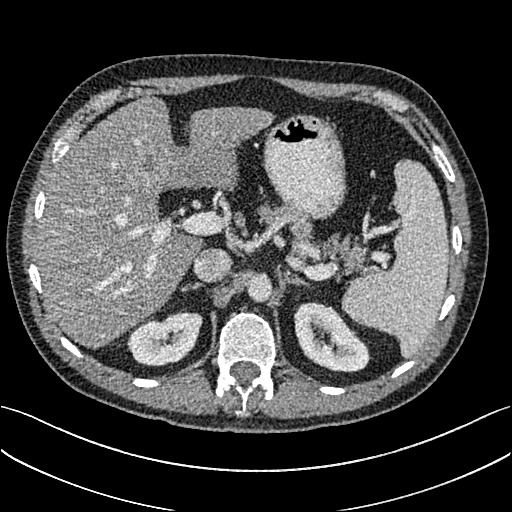

To demonstrate the effectiveness of the proposed network, we perform the qualitative comparisons over three representative abdominal images presented in Figs. 3, 5 and 7. For better evaluations of the image quality with different denoising models, zoomed regions-of-interest (ROIs) are marked by red rectangles and shown in Figs. 4, 6 and 8 respectively. Note that all results from different denoising models focus on two aspects: content restoration and noise-reduction. All CT images in axial view are displayed in the angiography window [-160, 240]HU.

The real NDCT images and corresponding LDCT images are presented in Figs. 3a and 3b. As observed, there are distinctions between ground truth (NDCT) images and LDCT images. Figs. 3a and 7a show the lesions/metastasis. Fig. 5a presents focal fatty sparing/focal fat. In Figs. 4a, 6a and 8a, these lesions can be clearly observed in NDCT images; in contrast, from Figs. 4b, 6b, and 8b, it can be seen that the original LDCT image is noisy, and lacks structural features for task-based clinical diagnosis. All adopted denoising models suppress noise to some extent.

From Figs. 7 and 8, we can see mean-based and SL-based methods work well with effective noise suppression and artifact removal. However, the illustrations in Fig. 8 show that these methods blur the local strutural features. Our proposed SMGAN-based methods present a better edge preservation than the competing methods.

In Figs. 7 and 8, it can be found that the SMGAN-based methods can achieve better anatomical feature preservations and visual quality than other state-of-the-art methods.

Figs. 7 and 8 demonstrate that the SMGAN-3D can be used to provide improved anatomical feature preservation over other state-of-the-art methods.